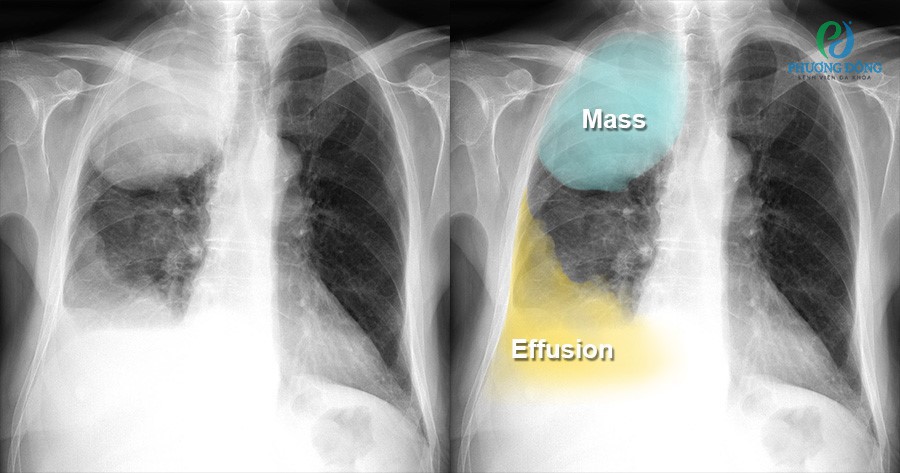

Tràn dịch và tràn khí màng phổi

Trong khoang màng phổi bình thường có khoảng 10–15ml dịch. Khi lượng dịch vượt quá mức này, gọi là tràn dịch màng phổi. Trên phim X-quang ngực thẳng, tình trạng này chỉ được nhận thấy rõ khi dịch đạt từ 175ml trở lên. Nếu dịch ở mức trung bình, hình ảnh X-quang sẽ cho thấy đường cong lõm hướng lên (đường cong Damoiseau), góc sườn hoành bị mất hoặc trở nên tù. Khi dịch nhiều, một bên phổi có thể bị che mờ hoàn toàn.

Tràn khí màng phổi xảy ra khi khí lọt vào giữa lá thành và lá tạng và đi vào khoang màng phổi. Thông thường khoang màng phổi hoàn toàn không có khí. Trên X-quang, hình ảnh thường là vùng tăng sáng, không thấy bóng mạch máu phổi. Phổi bị ép lại, đường viền lá tạng hiện rõ, khoang liên sườn giãn rộng, tim và trung thất bị đẩy sang phía đối diện, vòm hoành hạ thấp.

Tràn dịch và tràn khí màng phổi trên X-quang